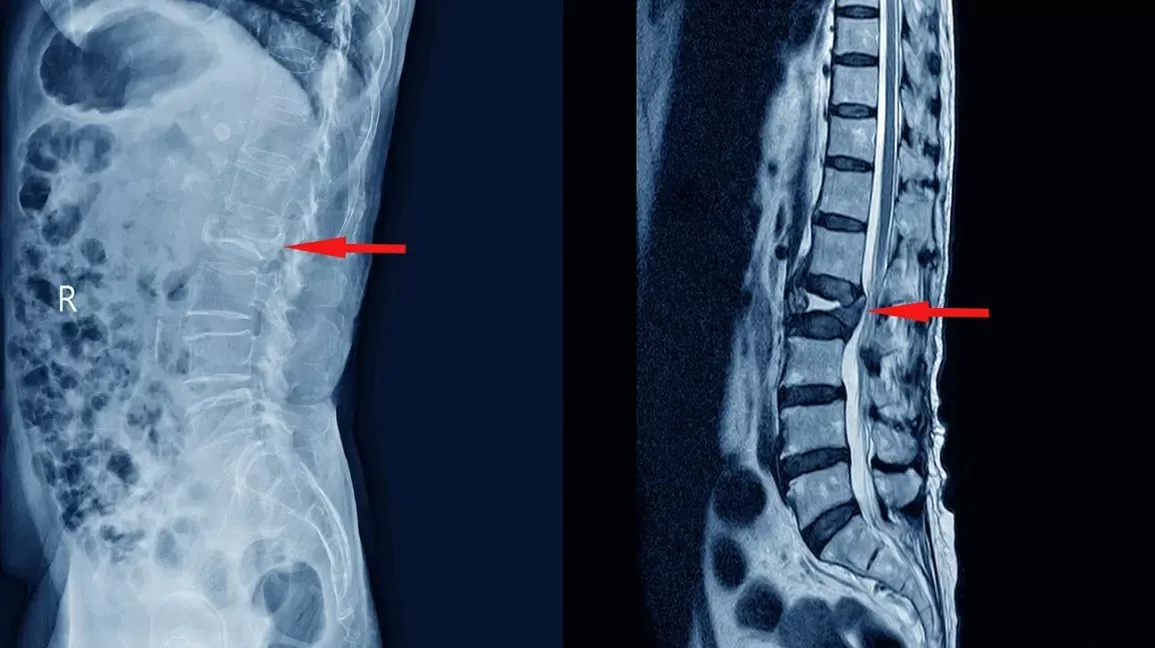

X-ray and MRI scans showing abnormalities in the spine, indicated by red arrows.

An MRI cannot tell you which disc herniation is causing pain and which is incidental. It can’t identify inflammation in the posterior annular fibers. It can’t show which of multiple potential pain generators is creating symptoms. It can’t distinguish between nerve compression that causes leg pain and annular tears that cause back pain.

Yet most physicians look at an MRI, see a disc herniation, and conclude that’s the source of pain. That approach fails for most patients with chronic back pain, because the actual pain generator isn’t the disc herniation itself – it’s the tear in the posterior annulus where that herniation is stuck, causing chronic inflammation.